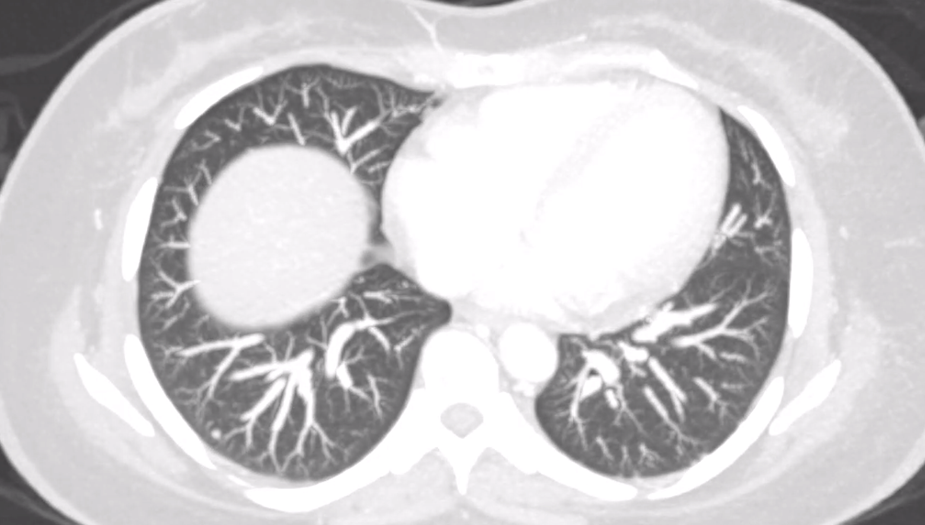

A low-dose 1-mg overnight dexamethasone suppression test produced an elevated serum cortisol of 991.03 nmol/L, showing unsuppressed morning cortisol, with an ACTH level of 577 pg/mL (reference, 7.2–63.3 pg/mL). Because of the markedly elevated ACTH, magnetic resonance imaging of the brain was performed to evaluate for a pituitary source but was negative (Figure 1). Cortisol levels remained elevated at >1750 nmol/L after the 8-mg high-dose dexamethasone suppression test, suggestive of an ectopic source.

Figure 1. Coronal view of a brain magnetic resonance imaging with contrast showing normal pituitary gland.